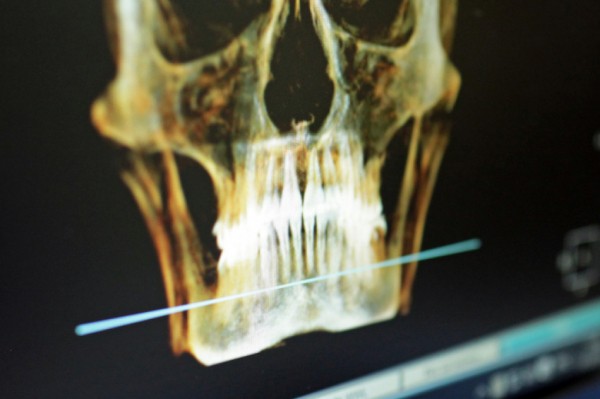

В этом году доктор Грег Молони, клинический доцент Университета Британской Колумбии, провёл уникальную операцию, в ходе которой в глаз Чапмана был имплантирован его собственный зуб. Пациент признаётся, что вновь начал ценить простые радости жизни и испытывает почти эйфорию от возвращения зрения.

Метод, известный как tooth-in-eye или остео-одонто-кератопротезирование, применяется в исключительных случаях, когда стандартные пересадки роговицы невозможны. Как объяснил доктор Висенте Диас из Yale School of Medicine, при некоторых заболеваниях, например, синдроме Стивенса-Джонсона, иммунная система разрушает стволовые клетки, отвечающие за прозрачность роговицы, и обычные методы не работают.

В ходе операции у пациента извлекают клык вместе с частью кости, формируют из него блок толщиной 4 мм, в который вставляют пластиковую оптическую линзу. Затем этот комплекс временно помещают в щёку или веко, чтобы ткани обросли имплантат. После этого в передней части глаза создают отверстие для установки конструкции, а часть слизистой изо рта используют для покрытия зуба, придавая новому глазу розоватый оттенок. Если сетчатка и зрительный нерв здоровы, свет вновь попадает на сетчатку, и зрение возвращается.